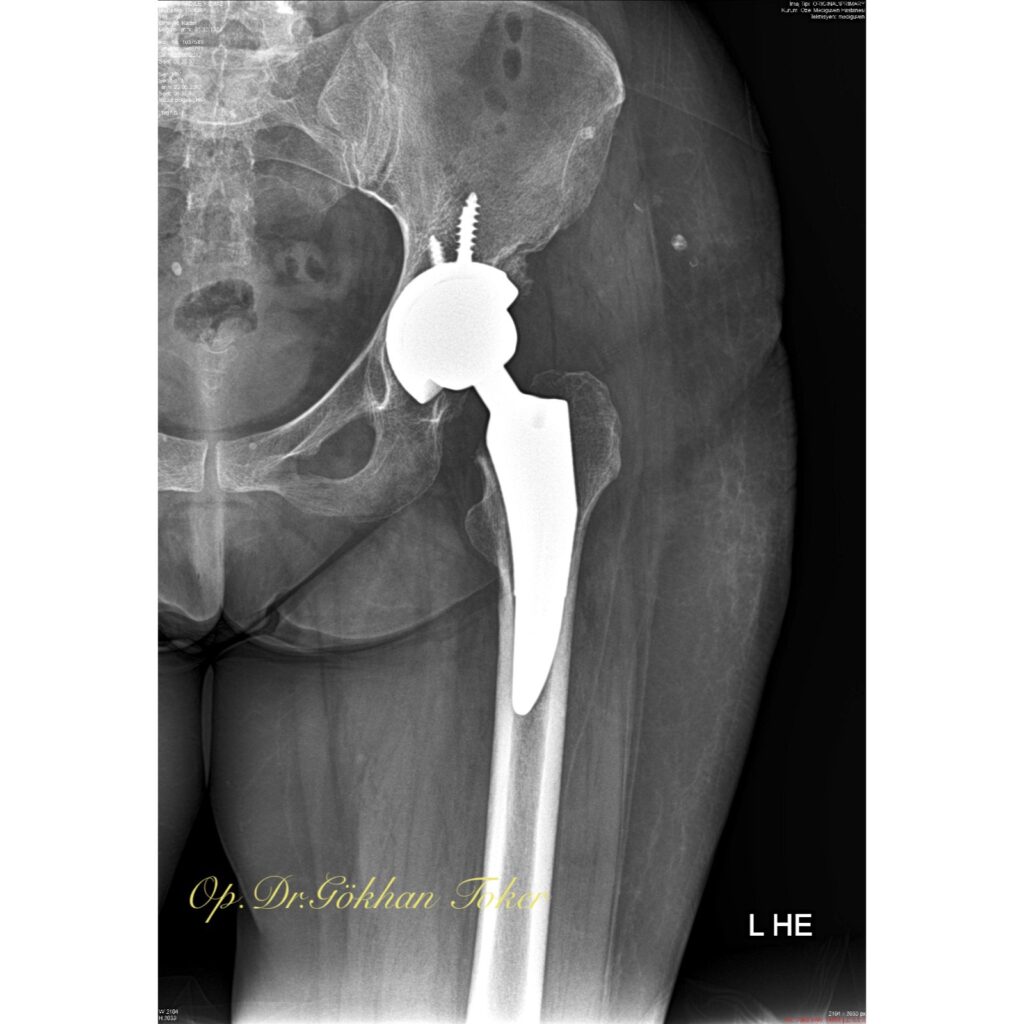

V.K.